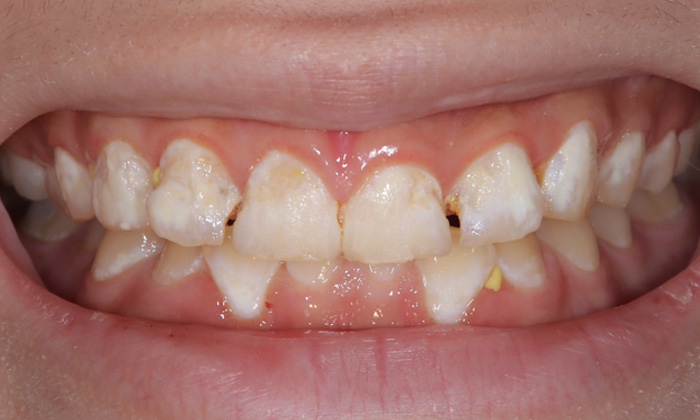

治療前

こちらの患者さまは、他院にて「酷い虫歯なので、うちで行う場合は神経を取る治療になります」と言われたそうです。まだ19歳でお若いこともあり神経を取ることをためらわれ、他院の歯科医師が当院への紹介状を書いてくださり、来院されました。

ご自身でも正常な歯ではなく「歯に穴があいていて変な感じ」と思われていたそうです。

患者さまの歯はとても脆くなっていて、歯が溶けて白くなっている部分もありました。食生活や嗜好品についてお話を伺ったところ、「エナジードリンクが好きで、日常的に飲んでいる」とのことでした。また、ブラッシングもあまりしていないとのことで、口腔内環境はかなり悪い状態です。

まずは悪くなっている歯質のみを削りました。写真からも分かるように、残せた健康な歯はたったこれだけしかありません。その後、直接法コンポジットレジン修復という、歯に直接素材を接着する方法を行いました。歯のすき間や表面を埋め、機能性や見た目を整えました。